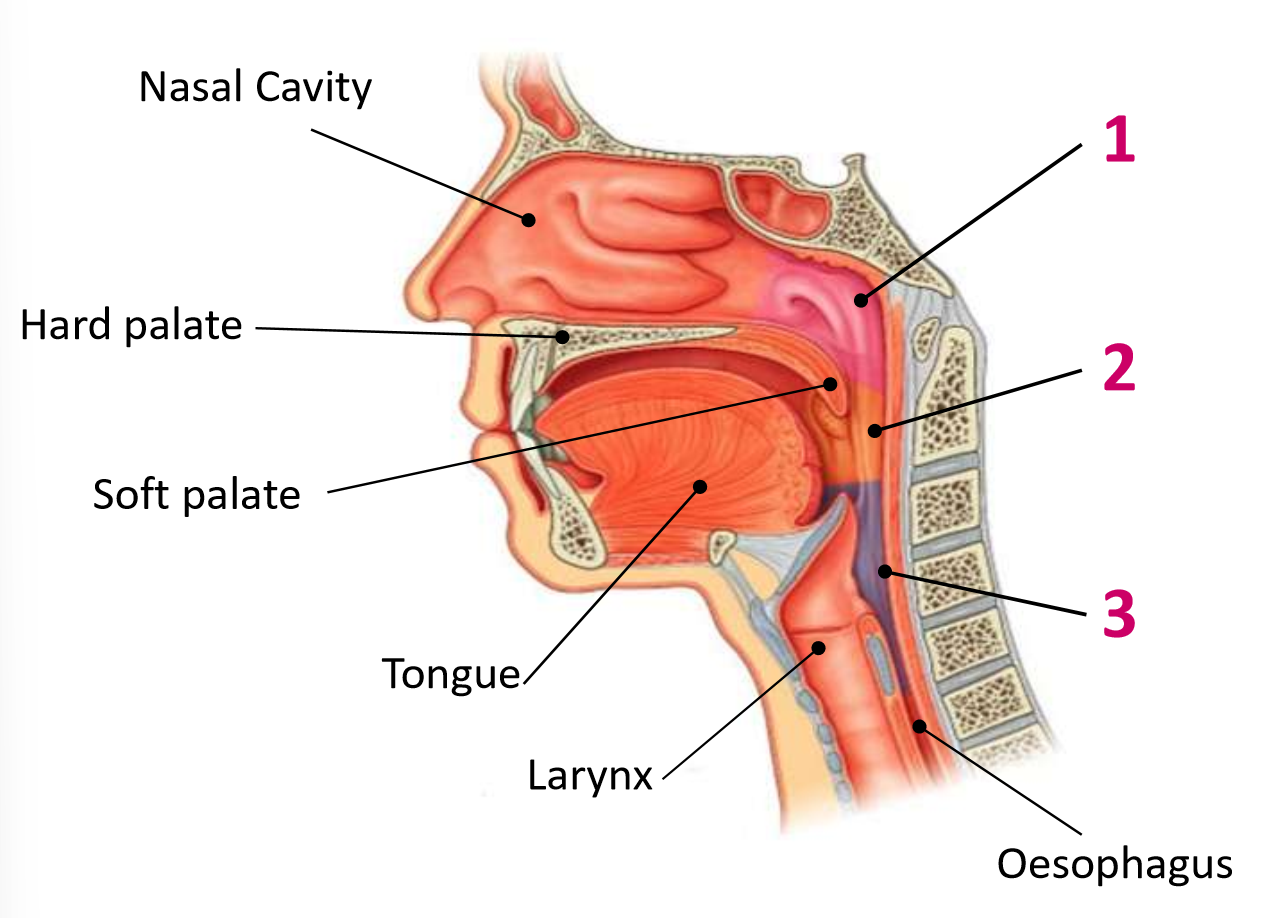

Which area of the head and neck do 1, 2, and 3 make?

pharynx

What region is 1?

nasopharynx

What region is 2?

oropharynx

What region is 3?

laryngopharynx

What is the anterior wall of 1?

posterior nasal choanae

What is the roof of 1?

body of sphenoid and basilar part of occipital

What is the posterior wall of 1?

anterior arch of atlas covered in pharyngobasilar fascia

What is the floor of 1?

soft palate

What is the anterior wall of 2?

oropharyngeal isthmus

What is the roof of 2?

soft palate

What is the floor of 2?

pharyngeal part of tongue and glossoepiglottic fold

What is the posterior wall of 2?

C2 and upper C3

What are the lateral walls of 2?

palatoglossal and palatopharyngeal arches